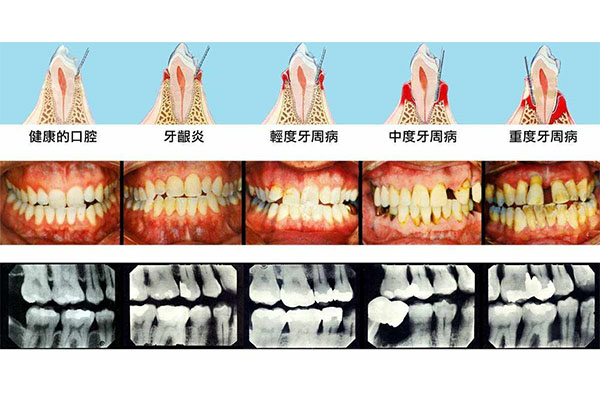

不建议忽视慢性智齿冠周炎。虽然短期内症状可能减轻,但炎症反复发作会导致周围组织破坏,甚至引发颌骨骨髓炎、间隙感染等严重后果。因此,一旦出现持续疼痛、肿胀、张口受限等症状,应及时就医。